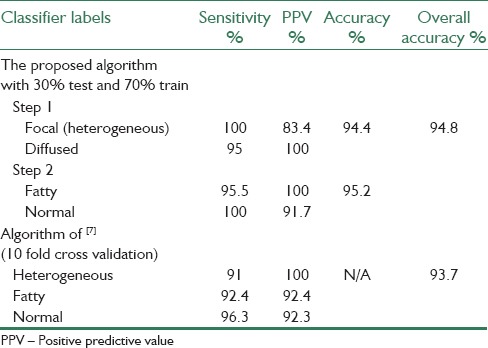

Select 30% of Dataset as Test Images

In the third experiment, the number of test samples is increased to evaluate this method more accurately. Therefore, the dataset is randomly partitioned to approximately 30% as test images and 70% as the training set. To reach this aim, the classification is performed using over 25 testing and 63 training images. This experiment is repeated with a hundred different random partitions in order to make any data bias associated with partitioning, insignificant. In this experiment, 25 overlapped blocks are used. The average of the Se and PPV of each class and Acc of each step of the system are shown in Table 2.

Table 2.

Results of the one-against-all nonhierarchical scheme over manually selected ROI by the use of leave one out cross validation

Tables 3 and 4 illustrate the Se and PPV of each class and the overall Acc using LOOCV method.

Table 4.

Average results of the third experiment by setting 30% of images as testing images and 70% as training images with hierarchical classification scheme and a comparison with results of 10 fold cross validation test of Minhas et al.[7]

The results of Table 2 show that with increasing the number of test images up to 30%, the Acc changes by only a small amount. Furthermore, Se of 100% for heterogeneous and normal livers in steps 1 and 2 respectively, depicts the quite detection of these cases. Diagnosis of the fatty case is also performed with high Se of 95.5%. Moreover, the high PPVs, specially, 100% in the fatty case; illustrate perfect precision in diagnosing fatty liver disease. The overall Acc of 94.8% in this experiment shows the performance and robustness of the proposed algorithm in comparison with[7] in its 10 fold cross validation experiment with the Acc of 93.7%. Table 2 illustrates a comparison between our proposed algorithm in the third experiment and 10 fold cross validation test of Minhas et al.[7]